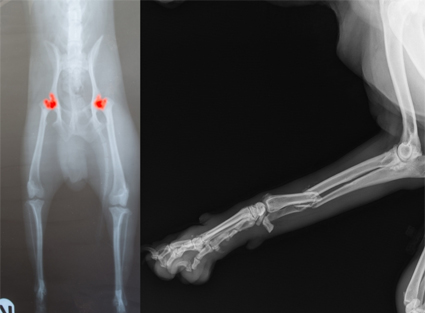

Radiología Ortopédica

- Diagnóstico de fracturas

- Displasia de cadera y codo

- Enfermedades articulares

- Evaluación prequirúrgica y postquirúrgica